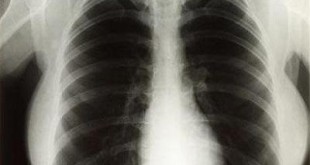

Phim X quang, cũng tương tự như phim chụp hình, được đặt phía sau bộ phận cơ thể cần chụp. Máy X quang sẽ chiếu tia X qua bộ phận cơ thể này. Các tia X nào gặp phim sẽ tạo hình. Càng nhiều tia X đến phim thì hình ghi được càng đen hơn. Vì vậy, các bộ phận đặc của cơ thể cản rất nhiều tia X sẽ cho hình trắng (ví dụ như xương) trong khi những bộ phận cơ thể rỗng hoặc đầy khí sẽ cho hình đen (ví dụ như phổi). Các mô mềm (ví dụ như cơ hoặc các tạng đặc trong cơ thể) sẽ cho hình ảnh có mức độ xám khác nhau tuỳ theo đậm độ của chúng.

Hình X quang thông thường sẽ cho thấy gì?

- Xương, răng, gãy xương và các bất thường khác của xương.

- Khe khớp và một số bất thường của ổ khớp, ví dụ như thoái hoá khớp.

- Kích thước và hình dạng của tim. Vì vậy, có thể phát hiện được một số bệnh tim.

- Thay đổi đậm độ mô mềm.

Ví dụ, một khối u phổi đặc hơn nhu mô phổi, sẽ cho thấy hình ảnh bóng mờ trên X quang. Một khối u vú đặc hơn mô vú bình thường sẽ cho thấy hình ảnh bóng mờ trên X quang vú (nhũ ảnh ).

- Tụ dịch, trong phổi hoặc ruột chẳng hạn, có thể sẽ cho hình ảnh bóng mờ với độ xám khác với màu đen chứa đầy khí của nhu mô phổi bình thường hoặc ruột trống.